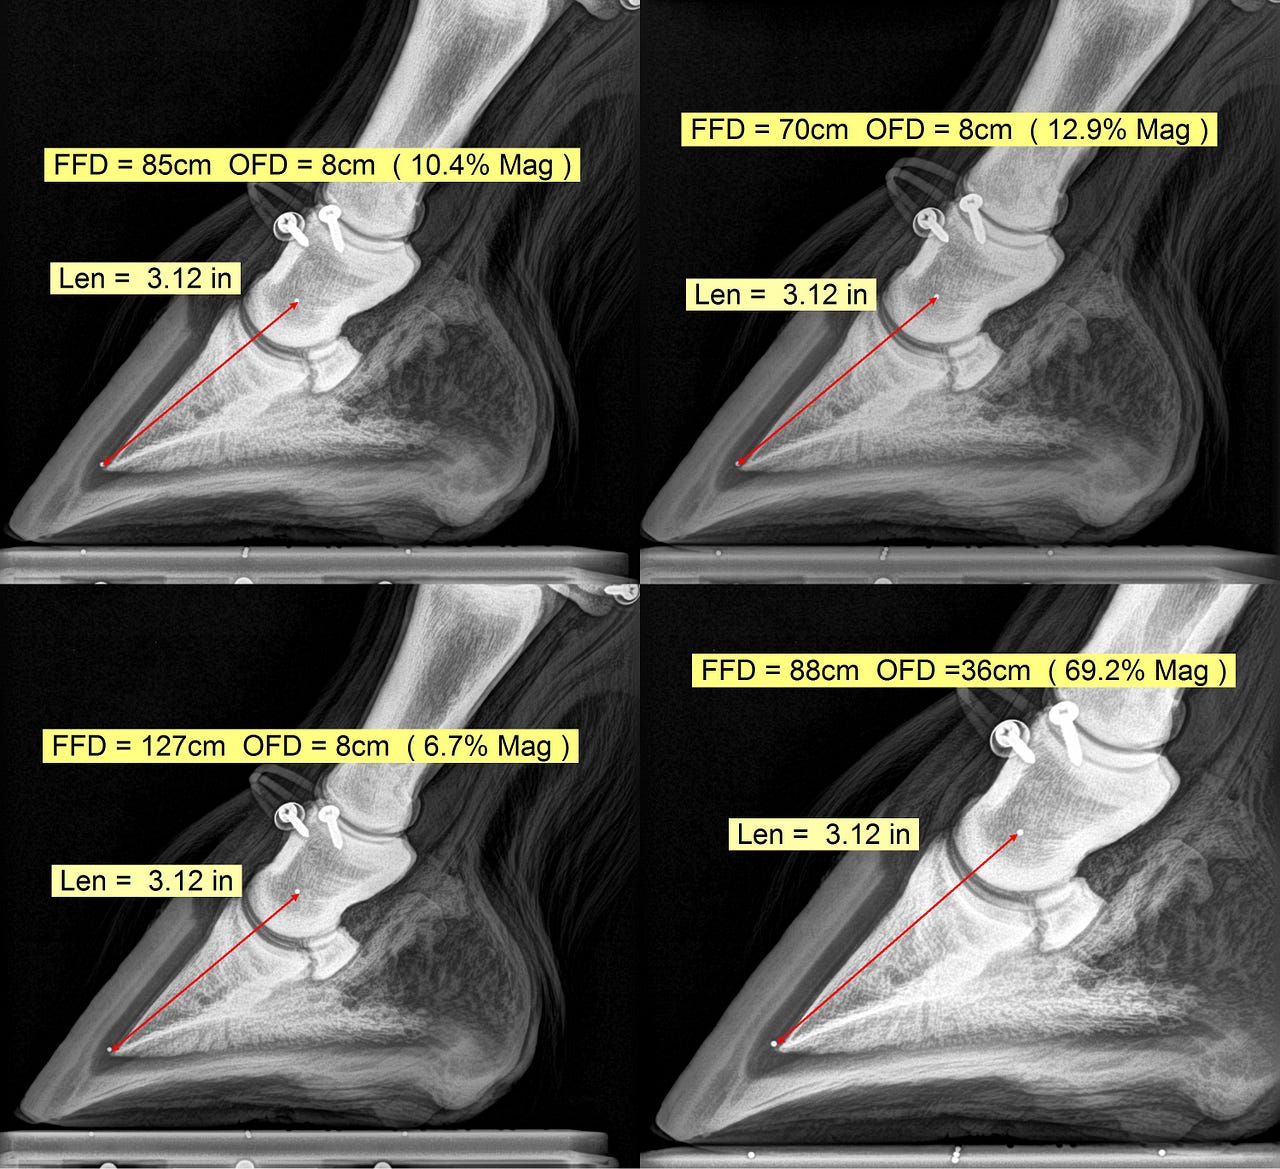

Metron Hoof Xray Mark Ups (2 feet series) Six BarTherapy

Measuring the Equine Hoof in Radiographs — a Focus on Calibration by Horse Hoof X Ray Cost Computed tomography (ct), diagnosing hoof lameness. Carried out at the vet hospital so no call out. i paid nearly £1000 for a lameness check and x rays of hocks, stifles and an ultrasound of the suspensories. learn about the machines and technologies your veterinarian can use to look inside your horse, including mri, ct, pet scans, and more.. Horse Hoof X Ray Cost.

From medium.com

Measuring the Equine Hoof in Radiographs — a Focus on Calibration by Horse Hoof X Ray Cost i paid nearly £1000 for a lameness check and x rays of hocks, stifles and an ultrasound of the suspensories. Your horse may need to be sedated, depending on their temperament, to ensure the best quality image. Carried out at the vet hospital so no call out. Computed tomography (ct), diagnosing hoof lameness. learn about the machines and. Horse Hoof X Ray Cost.